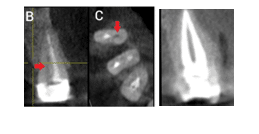

Radiographs should be used to give you an idea about the anatomy of the tooth and possible variations.

CBCT is very useful for identifying complex anatomy.

Ultrasonic tips are helpful in locating hidden canals in a complex anatomy.

Re-evaluation If missed canals are suspected, consider taking additional radiographs from different angles, or utilize cone-beam C.T (CBCT). Use of magnification Dental loupes or operating microscopes are important for searching for small or hidden canals Re-access the tooth Reopen the access cavity to explore the canal system Use fine-sized burs and hand files to detect hidden canals Slightly expand the access cavity for better visibility Gentle negotiation Use small k-files Use ultrasonic tips To negotiate small canals. |